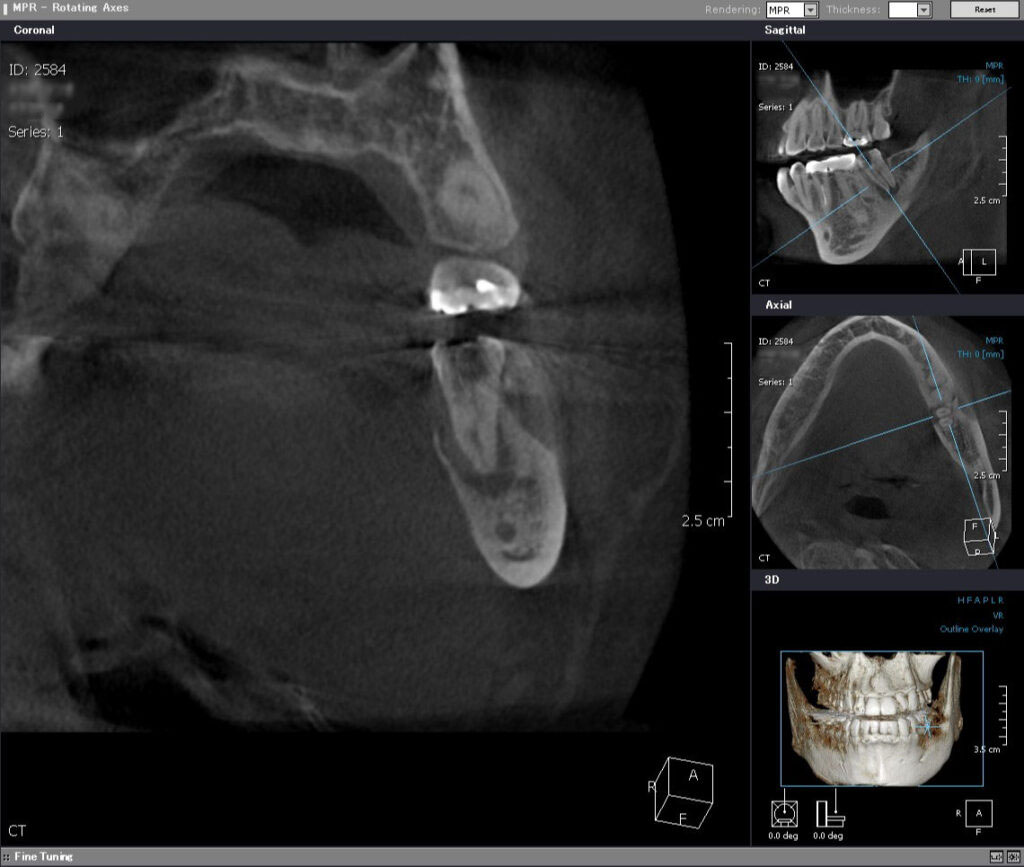

術前CT前頭断

根っこの先の黒い骨透過像(吸収像)をはっきりと認め、特に舌側が著しいです。そのため、舌側の歯茎が腫れてきたと考えられます。一般的には、抜歯と診断されるでしょう。